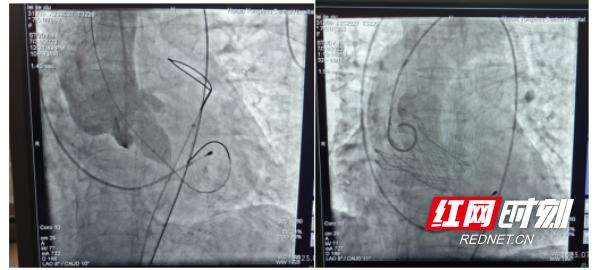

8月1日上午九时,在麻醉满意后,心血管内科结构性心脏病团队为患者置入临时起搏器,准确穿刺双侧股动股,左侧股动脉辅助入路送入抓捕器,辅助右侧股动脉主入路瓣膜输送器顺利跨瓣,在DSA及食道超声引导下,准确定位、释放TaurusElite瓣膜,测量无明显压差及瓣周漏,无血管损伤后,使用ProGlide缝合器缝合股动脉。手术顺利,患者术后第二天即可床旁活动,对治疗效果非常满意。